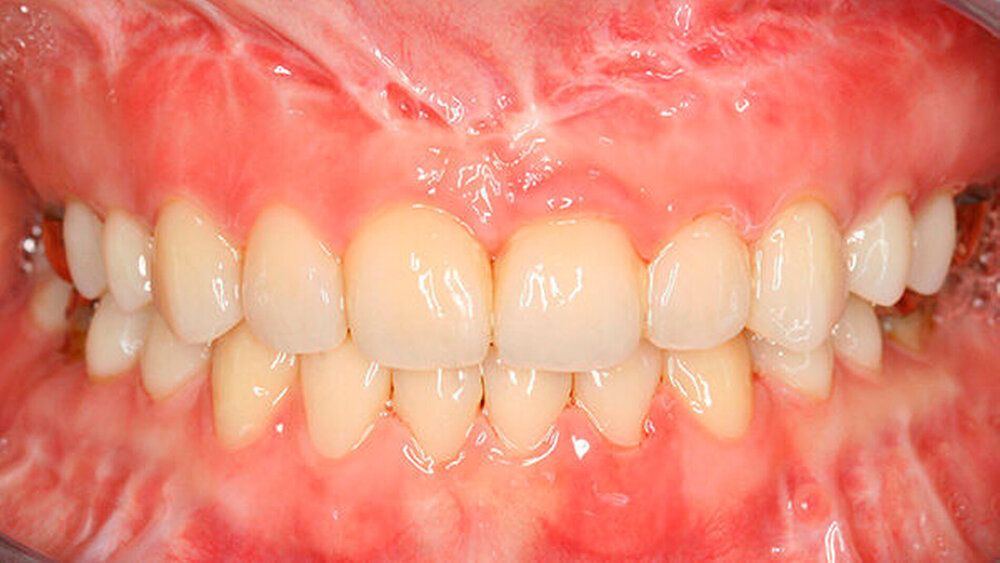

a) Dentinogenesis imperfecta. Da alle Zähne betroffen sind, ist von einer genetisch bedingten Fehlbildung auszugehen. Die Zähne der Patientin weisen zudem eine veränderte Farbe auf. Darüber hinaus sind Abplatzungen des Schmelzes vorzufinden. Trotzdem liegt keine Dentinogenesis imperfecta vor. Die Abplatzungen sind größtenteils geringfügig und zunächst oberflächlich, das heißt nicht unmittelbar bis zum Dentin. Die Farbänderung der Zähne entspricht nicht dem klassischen Bild einer Dentinogenesis imperfecta (siehe auch Abbildungen 3 und 4).